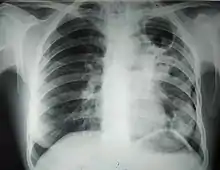

![]() Рентгенограмма органов грудной клетки больного туберкулёзом лёгких с распадом | |